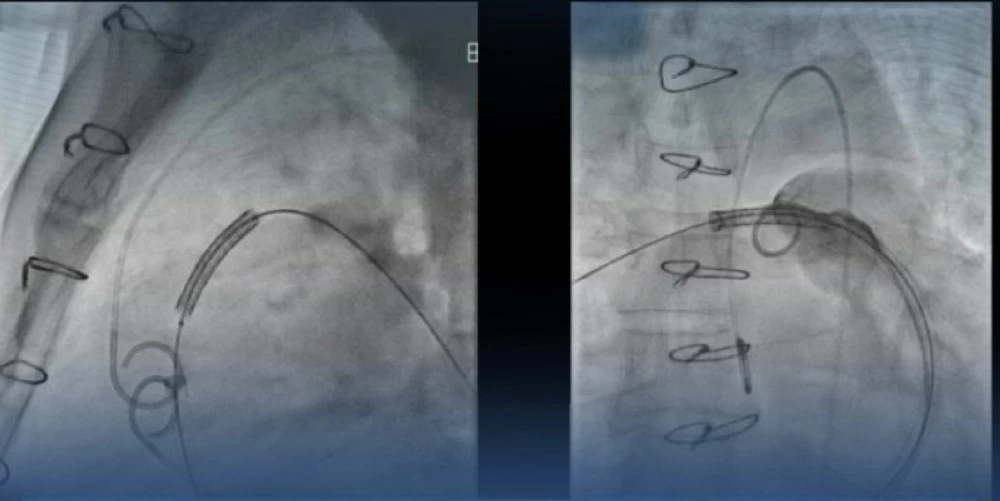

أجريت العملية باستخدام تصوير متقدم ودعامات عالية الضغط تضمن الدقة والنتائج المثالية، ليعزز هذا النجاح مكانة مركز القلب كوجهة علاجية رائدة في أمراض العيوب الهيكلية وصمامات القلب.

The procedure was performed using advanced imaging and high-pressure stents to ensure precision and optimal results, further enhancing the status of the heart center as a leading treatment destination for structural heart defects and valve diseases.